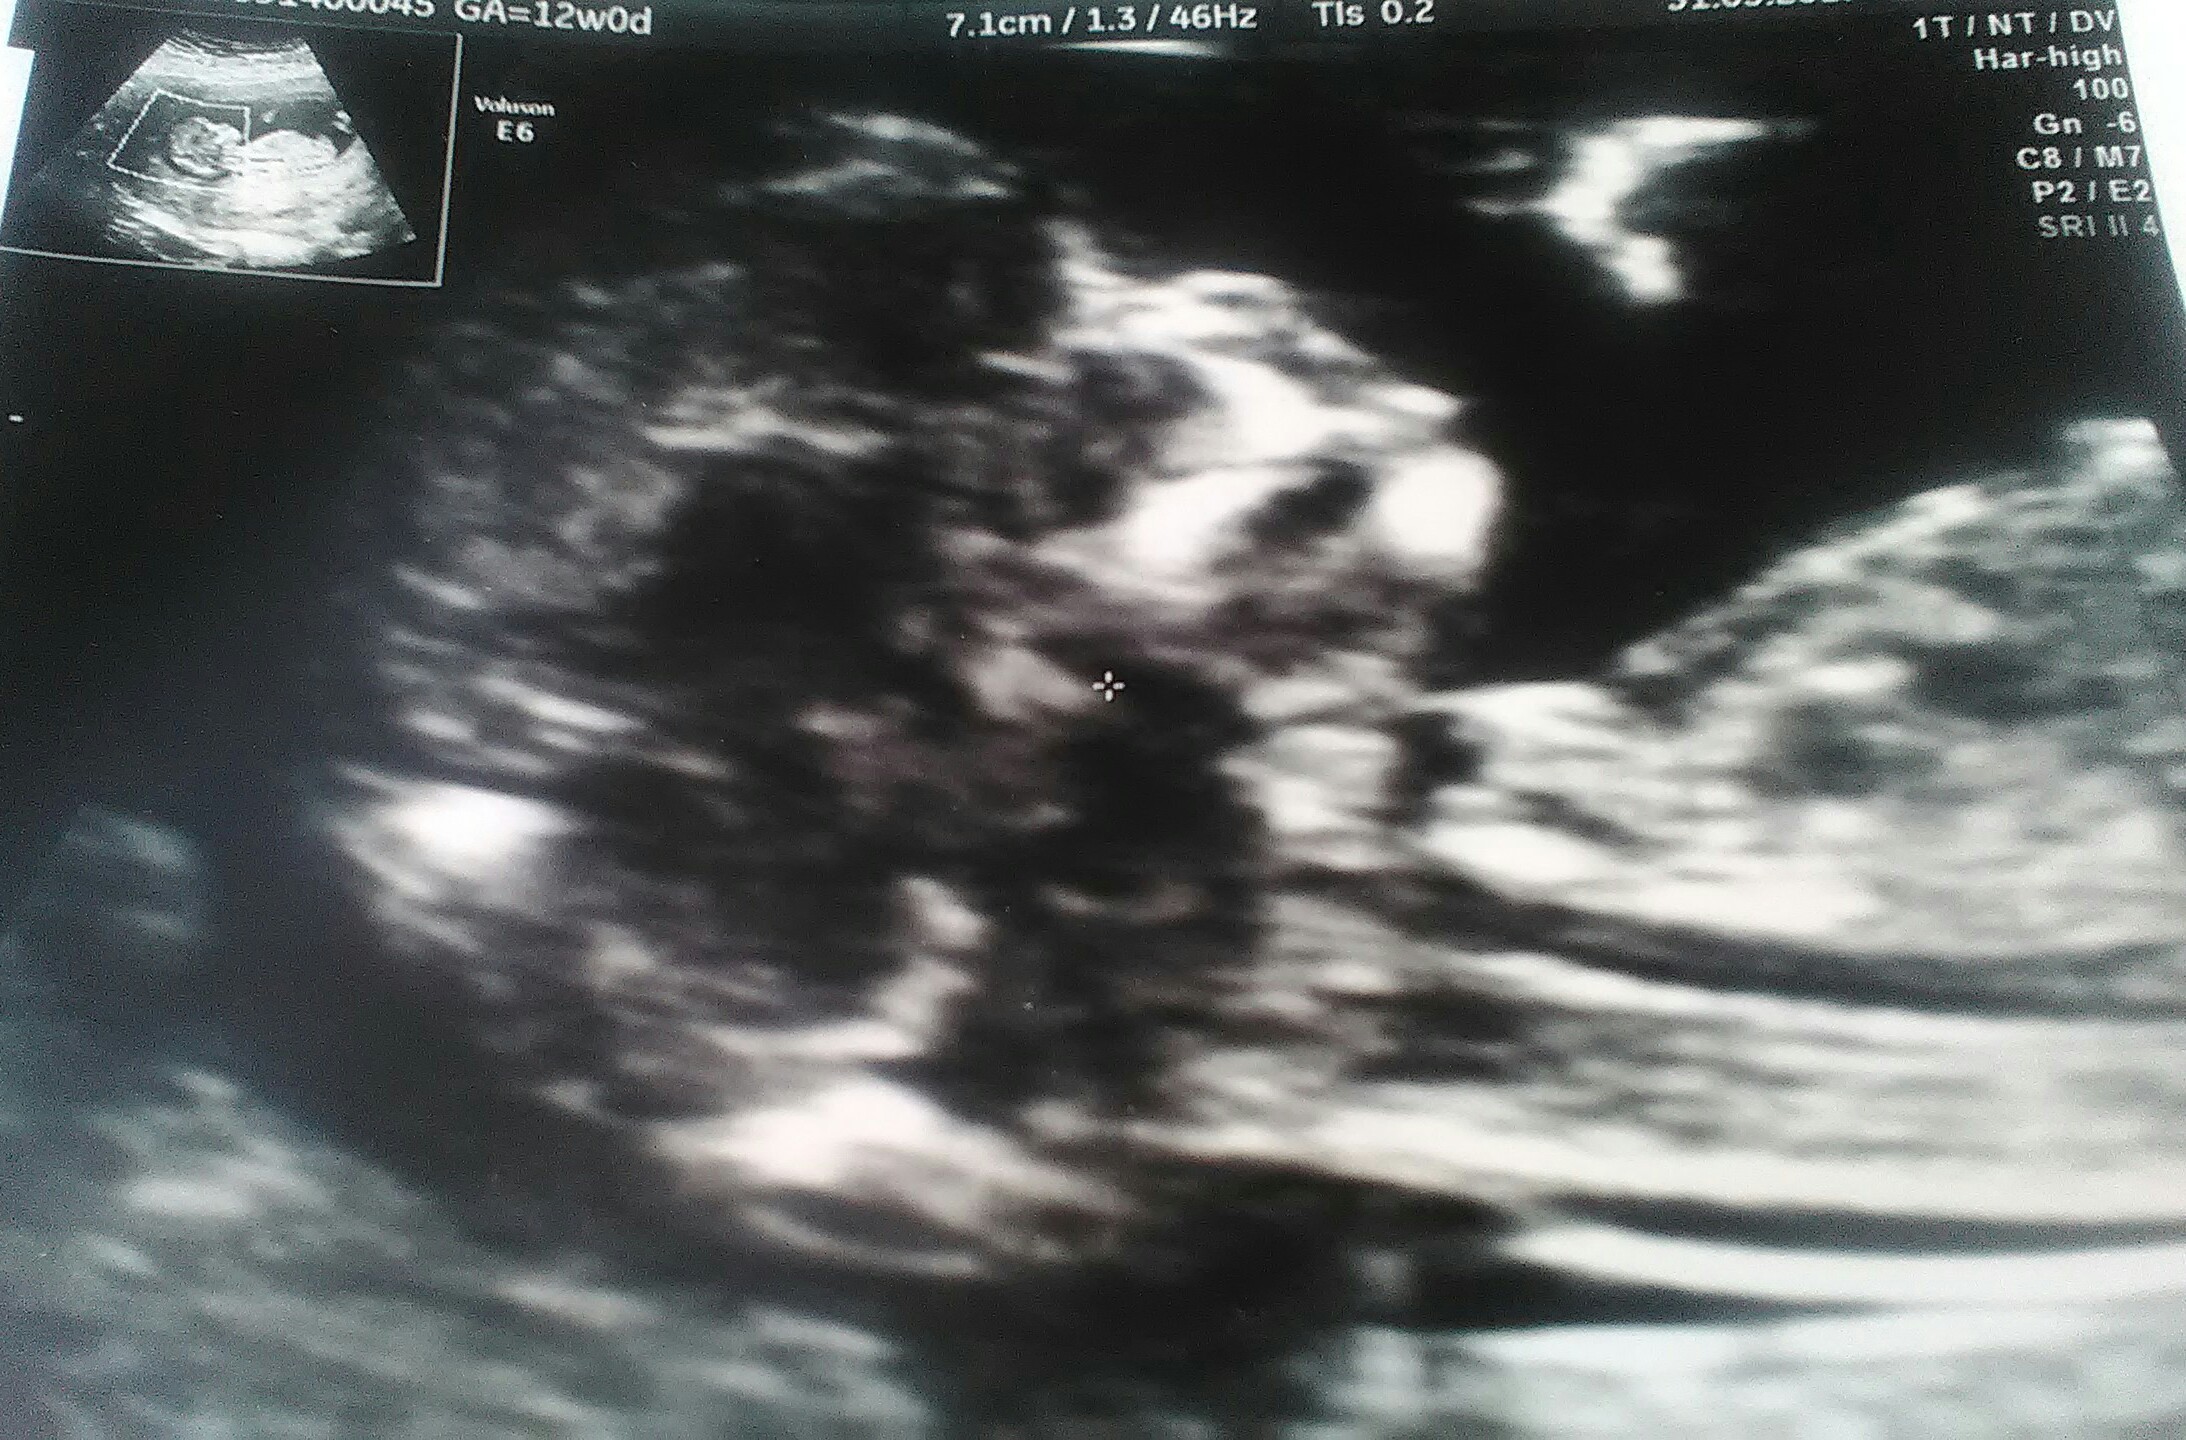

Po badaniach, zdrowe, książkowe 58mm szczęścia ☺

• P_20170531_125956_1.jpg

P_20170531_125956_1.jpg

750,7 KB · Wyświetleń: 110